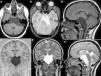

Los quistes aracnoideos son lesiones quísticas malformativas que contienen en su interior un líquido de características similares al líquido cefalorraquídeo. Constituyen alrededor del 1% de todos los procesos ocupantes de espacio a nivel intracraneal y, en los últimos años, su incidencia se ha incrementado ligeramente debido a la mejora en las técnicas de diagnóstico radiológico.

Aunque la mayoría de los quistes aracnoideos se sitúan en la cavidad craneal, especialmente en la región de la cisura de Silvio, un menor número de casos pueden localizarse a nivel espinal.

Realizamos una revisión sobre las diferentes técnicas de diagnóstico por imagen de los quistes aracnoideos, analizando la indicación de cada una de ellas en función de la localización y edad de los pacientes.